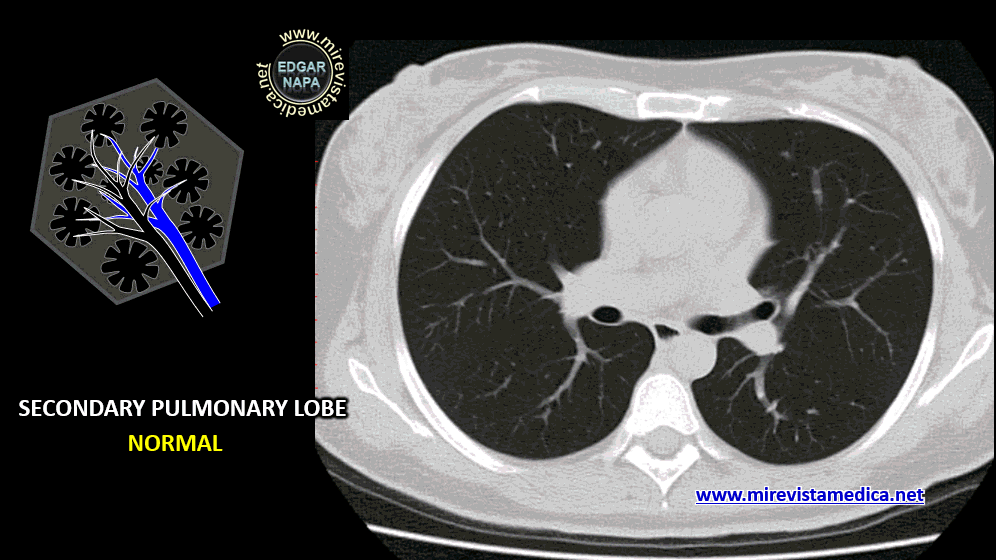

TOMOGRAFÍA COMPUTARIZADA (CT)